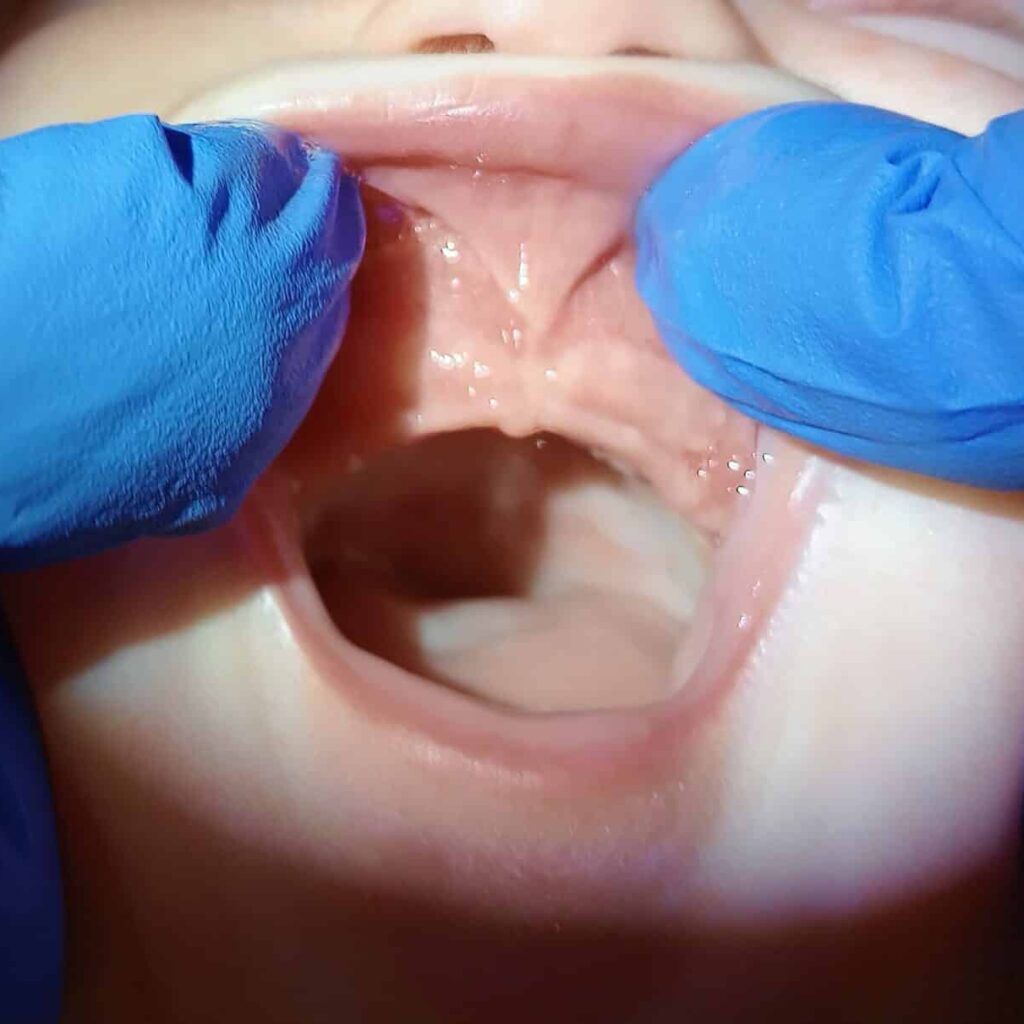

Posterior tongue tie pre surgery

Pre surgery Tongue tie